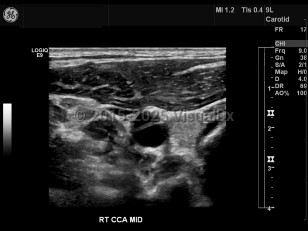

Carotid artery dissection

Carotid artery dissection is tearing of the carotid artery wall between the intimal and medial layers, resulting in an abnormal collection of blood or intramural hematoma. May compromise the arterial blood flow, causing ischemic stroke. Painful condition. Characteristic findings include headache and/or neck pain on the side of the dissection, periorbital headache / pain, miosis, ptosis, amaurosis fugax, tinnitus, facial numbness, dysgeusia, tongue paresis, and syncope. Caused by a weakness in the arterial wall. Sometimes the result of blunt trauma to the neck or head as a result of a sports injury, strenuous exercise, whiplash, childbirth, or sexual intercourse. Certain conditions may compromise the strength of the arterial wall, including Marfan syndrome, fibromuscular dysplasia, atherosclerosis, Ehlers-Danlos syndrome type 4, and homocystinuria.